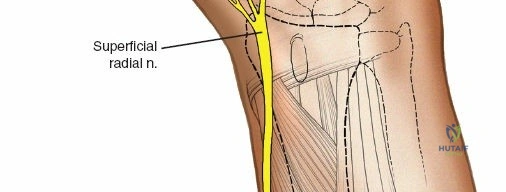

Radius Safe Zones

* Middle Third: Pins can be placed dorsolaterally. The superficial radial nerve (SRN) and cephalic vein must be protected.

* Distal Third: The SRN emerges from beneath the brachioradialis approximately 9 cm proximal to the radial styloid. Pins are typically placed at a 45-degree angle between the extensor carpi radialis longus (ECRL) and brachioradialis, or directly laterally. A mini-open approach is critical here.

Radius External Fixation

External fixation of the radial diaphysis requires meticulous attention to the superficial radial nerve and the posterior interosseous nerve.

Mid-to-Proximal Radius Pin Placement

1. Supinate the forearm to move the PIN dorsally and radially.

2. Make an incision over the dorsolateral aspect of the radius.

3. Dissect between the extensor carpi radialis brevis (ECRB) and the extensor digitorum communis (EDC).

4. Use retractors to carefully protect the PIN.

5. Insert the tissue sleeve, pre-drill, and place a 4.0 mm pin bicortically.

Distal Radius Pin Placement

1. Identify the interval between the brachioradialis and the ECRL.

2. Make a 2-3 cm longitudinal incision.

3. Carefully identify and retract the superficial radial nerve branches.

4. Place the drill sleeve directly on the radial styloid or slightly proximal, aiming ulnarward and slightly dorsally.

5. Insert 3.0 mm or 4.0 mm pins.

Neurovascular complications, while less common, carry significant morbidity. The radial nerve is at highest risk during humeral fixation, while the superficial radial nerve is frequently irritated or injured during distal radius fixation. Adherence to the mini-open technique, utilizing blunt dissection to the periosteum, is the standard of care to mitigate this risk.